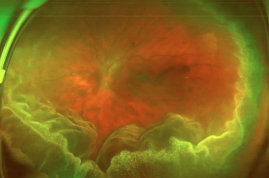

渗出性视网膜脱离

无裂口,因炎症、血管渗漏、肿瘤等导致液体积聚,使视网膜脱离,以管控原发病为主。

· 渗出性脱离:先治原发病,配合激光或药物促进复位。